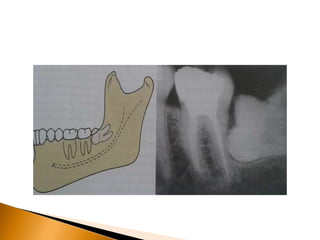

• 36.

A maioria dosesquemas de classificação é baseada na análise de radiografias. 1. A radiografia panorâmica mostra a imagem mais acurada da anatomia da região e é a escolha para o planejamento de terceiros molares impactados. 2. A radiografia periapical bem posicionada é adequada, desde que a maior parte do dente impactado esteja visível junto a importante anatomia adjacente. 3. A tomografia computadorizada é útil em casos onde as raízes de terceiros molares inferiores aparecem muito próximas ou sobrepostas ao canal alveolar inferior na radiografia panorâmica.